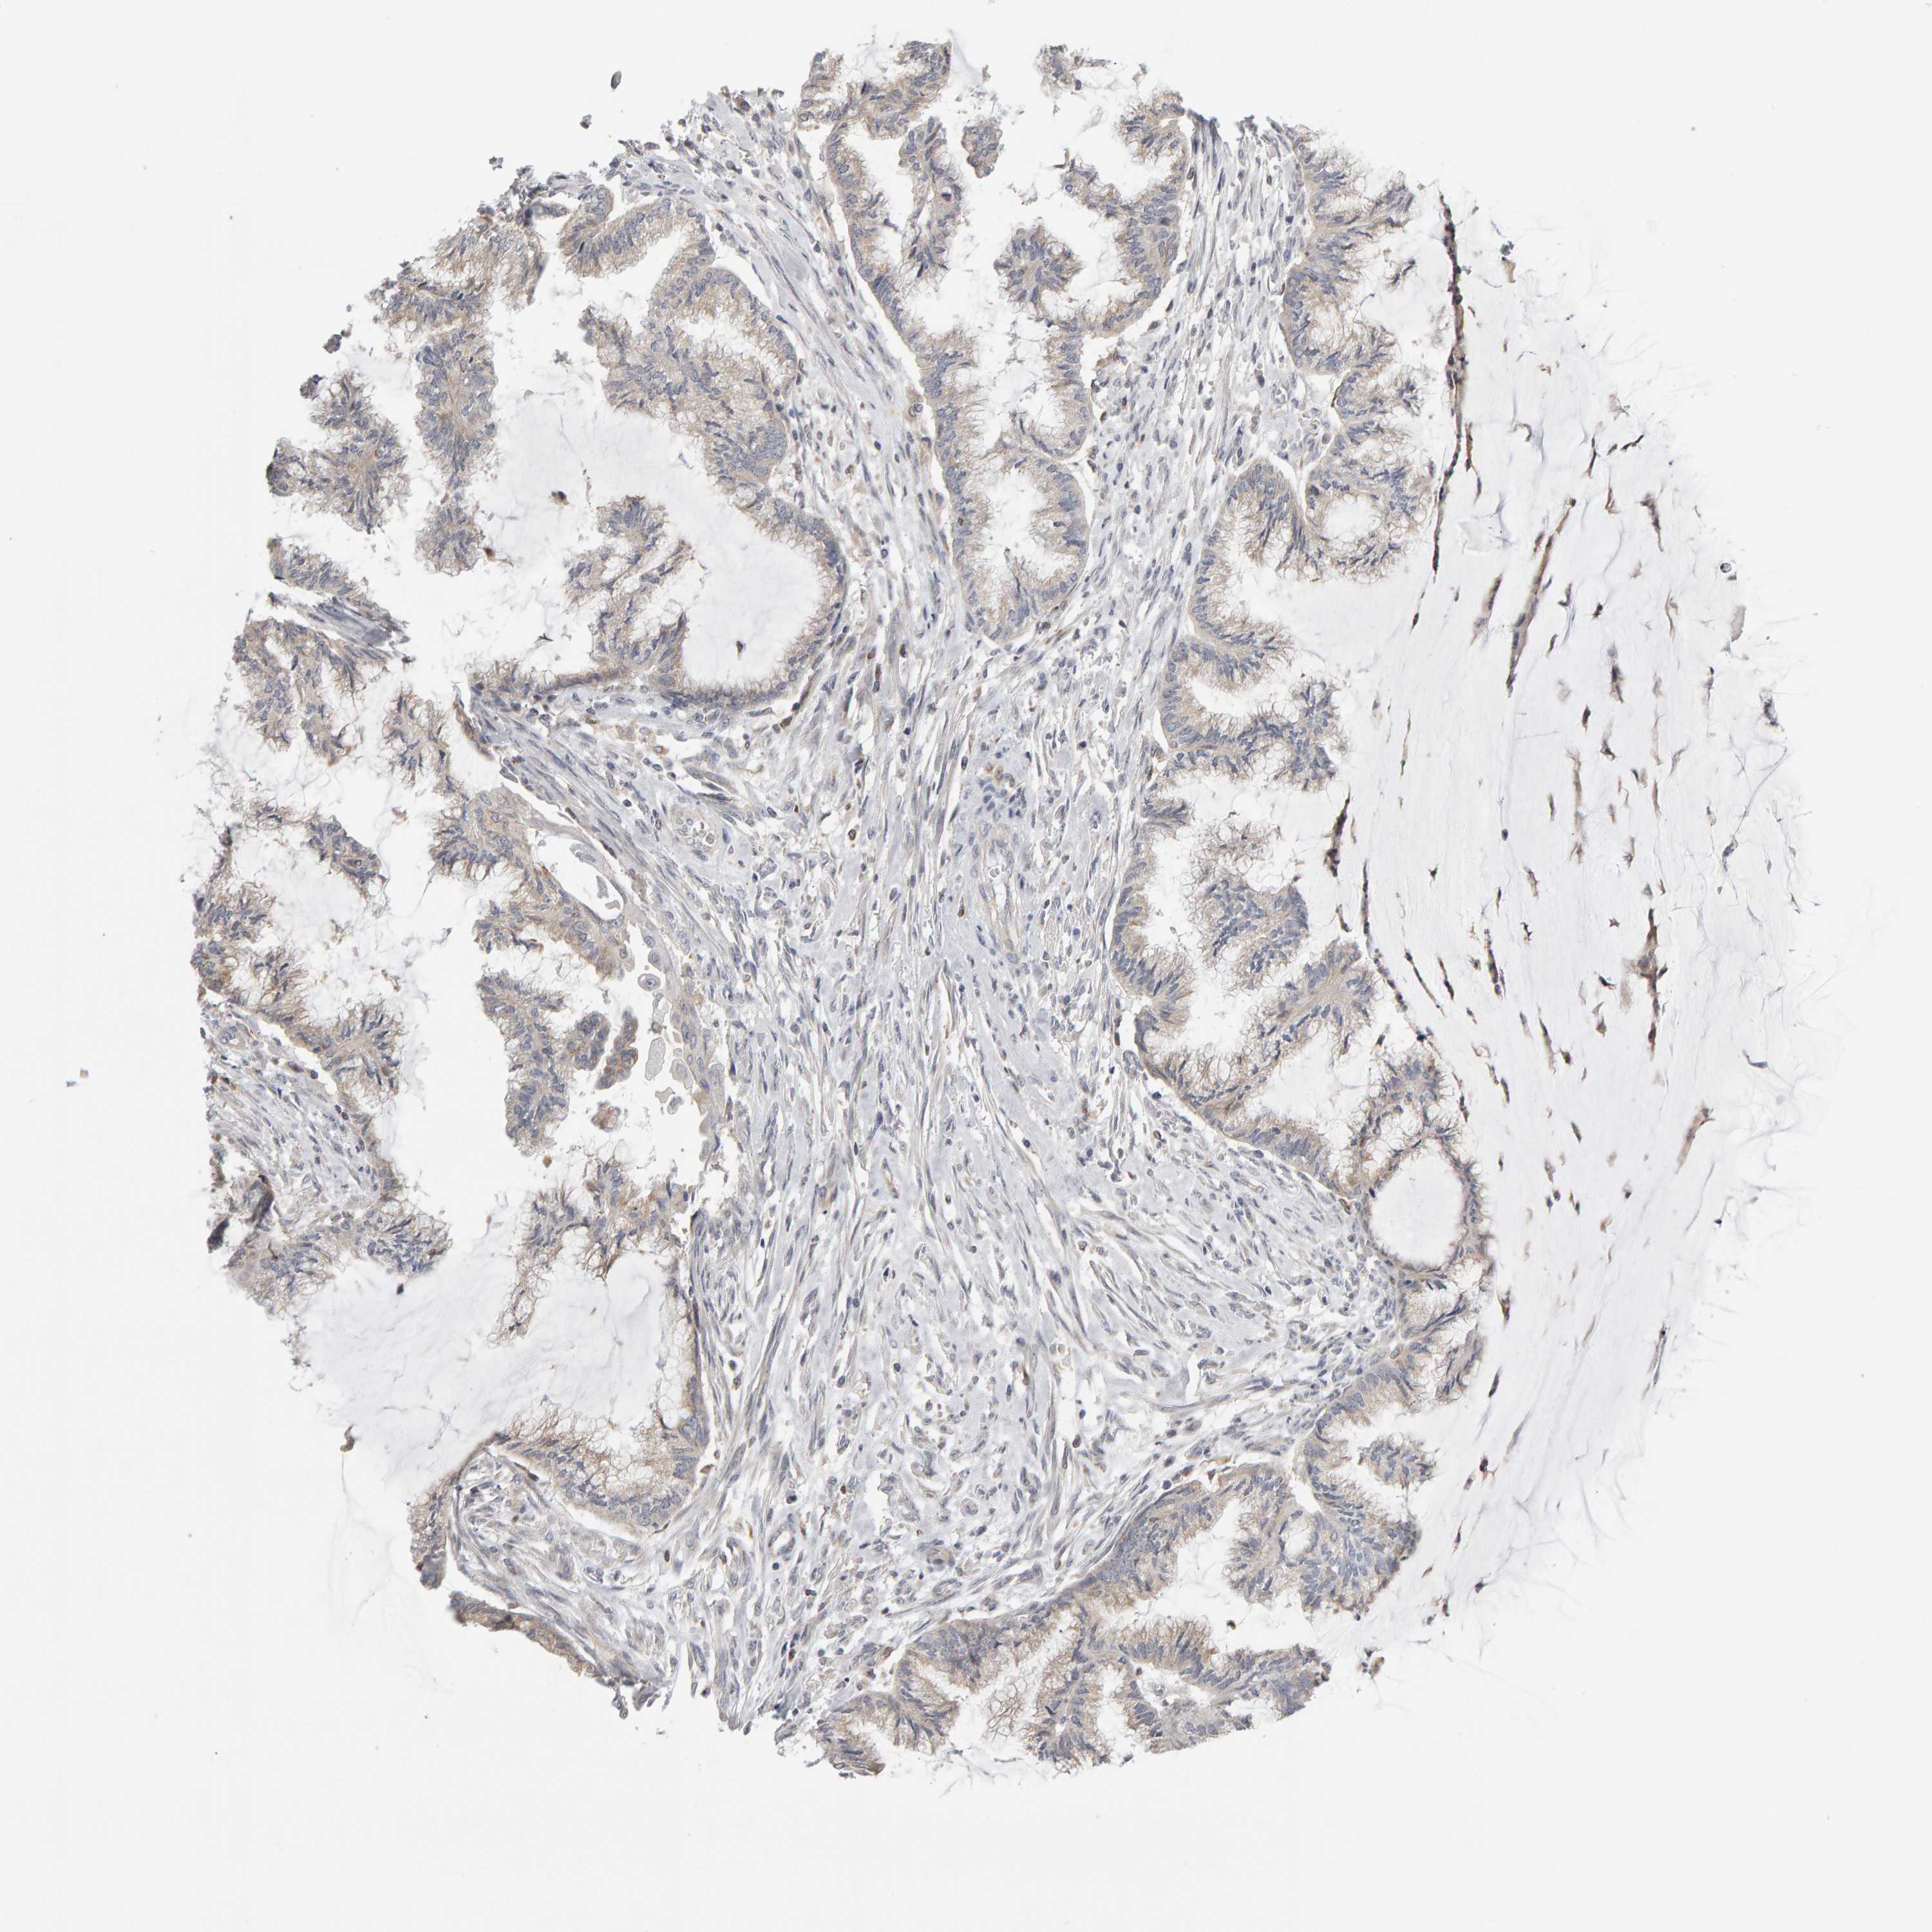

ENDOMETRIAL CANCER - Protein expressioni

A mouse-over function shows sample information and annotation data. Click on an image to view it in a full screen mode. Samples can be filtered based on level of antibody staining by selecting one or several of the following categories: high, medium, low and not detected. The assay and annotation is described here.

Note that samples used for immunohistochemistry by the Human Protein Atlas do not correspond to samples in the TCGA dataset.

Antibody stainingi

Antibody staining in the annotated cell types in the current human tissue is reported as not detected, low, medium, or high, based on conventional immunohistochemistry profiling in selected tissues. This score is based on the combination of the staining intensity and fraction of stained cells.

Each image is clickable and will lead to virtual microscopy that enables deeper exploration of all samples and also displays staining intensity scores, fraction scores and subcellular localization as well as patient and tissue information for each sample.

Antibody HPA023804

Antibody HPA075766

Staining

High

Medium

Low

Not detected

Intensity

Strong

Moderate

Weak

Negative

Quantity

>75%

75%-25%

<25%

None

Location

Nuclear

Cytoplasmic/membranous

Cytoplasmic/membranous,nuclear

Adenocarcinoma, NOS

Adenoma, NOS